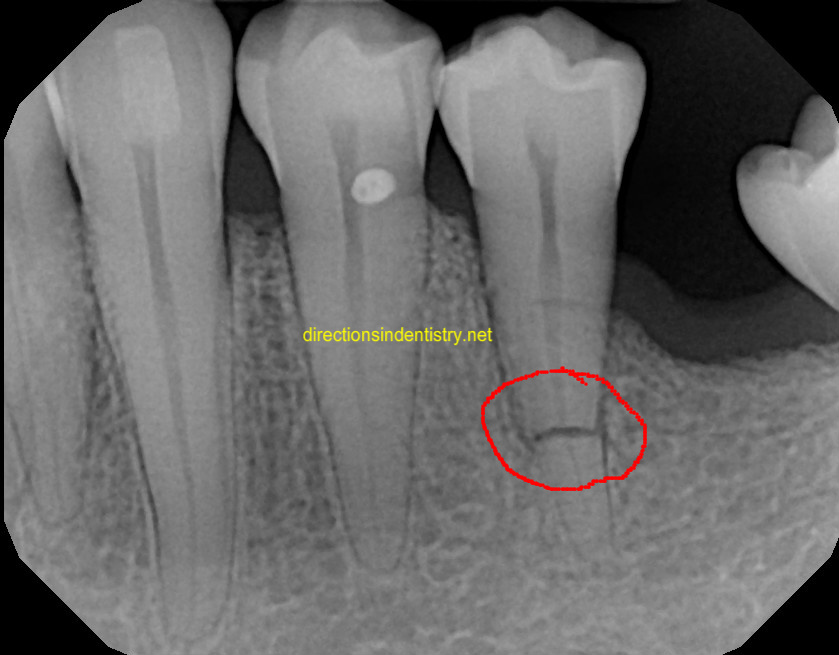

Анатомия: Межкорневая костная перегородка

Раздел: Галерея впечатлений